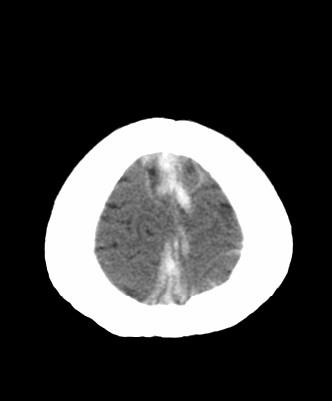

Timing of Injury: Can we use Cerebral Edema on CT?

 Loss of grey white juncture

 White cerebellar sign

 Pseudo Subarachnoid Hemorrhage

 Reversal of Basal Ganglia Sign

Timing of Injury on CT: EDEMA?

 Edema: first see in 1.2-2 hrs

Evident by 24 hours post injury

100%  Evolution over time helpful 1.5 hours 6 hours